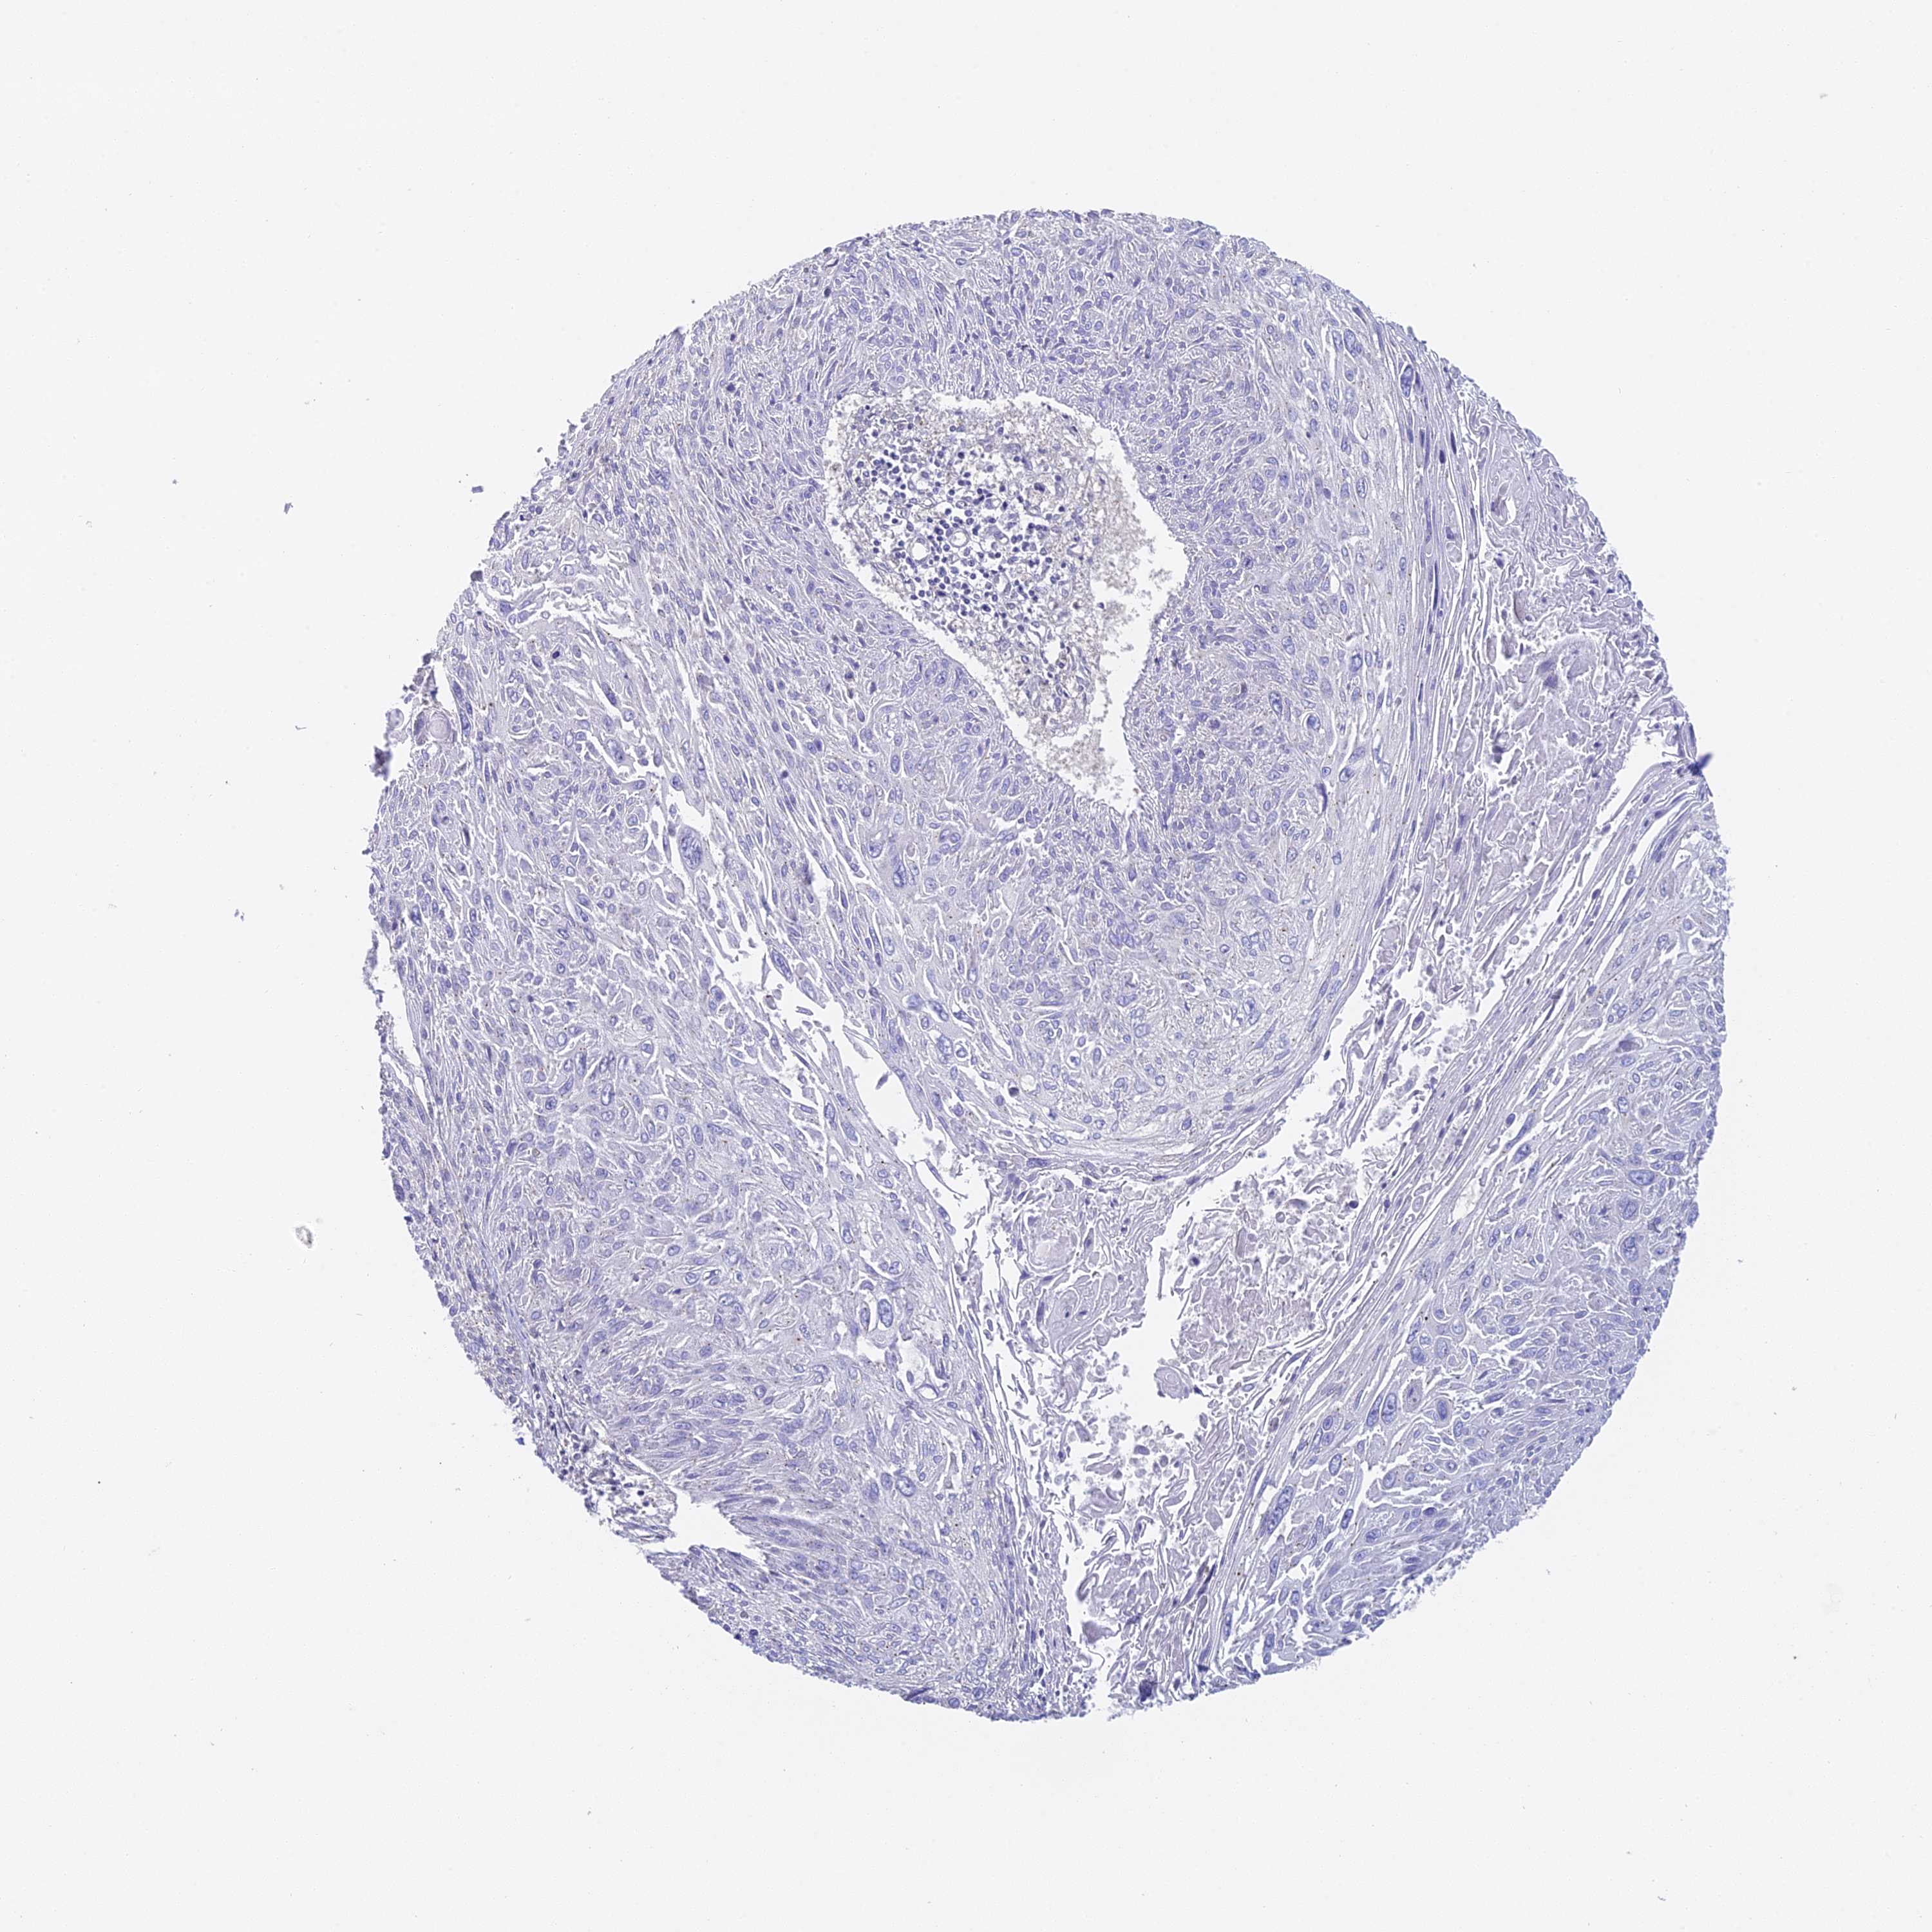

CERVICAL CANCER - Protein expressioni

A mouse-over function shows sample information and annotation data. Click on an image to view it in a full screen mode. Samples can be filtered based on level of antibody staining by selecting one or several of the following categories: high, medium, low and not detected. The assay and annotation is described here.

Note that samples used for immunohistochemistry by the Human Protein Atlas do not correspond to samples in the TCGA dataset.

Antibody stainingi

Antibody staining in the annotated cell types in the current human tissue is reported as not detected, low, medium, or high, based on conventional immunohistochemistry profiling in selected tissues. This score is based on the combination of the staining intensity and fraction of stained cells.

Each image is clickable and will lead to virtual microscopy that enables deeper exploration of all samples and also displays staining intensity scores, fraction scores and subcellular localization as well as patient and tissue information for each sample.

Antibody HPA043666

Antibody HPA050552

Staining

High

Medium

Low

Not detected

Intensity

Strong

Moderate

Weak

Negative

Quantity

>75%

75%-25%

<25%

None

Location

Nuclear

Cytoplasmic/membranous

Cytoplasmic/membranous,nuclear

Squamous cell carcinoma, NOS

Adenocarcinoma, NOS